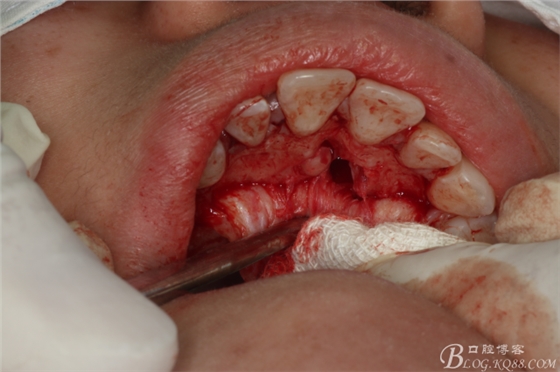

圖13.去骨、暴露11腭側(cè)部分多生牙

圖14.逐漸暴露出的多生牙

圖15.用微創(chuàng)挺取出右側(cè)上腭多生牙

圖16.拔除兩顆多生牙后的鼻腭管情況